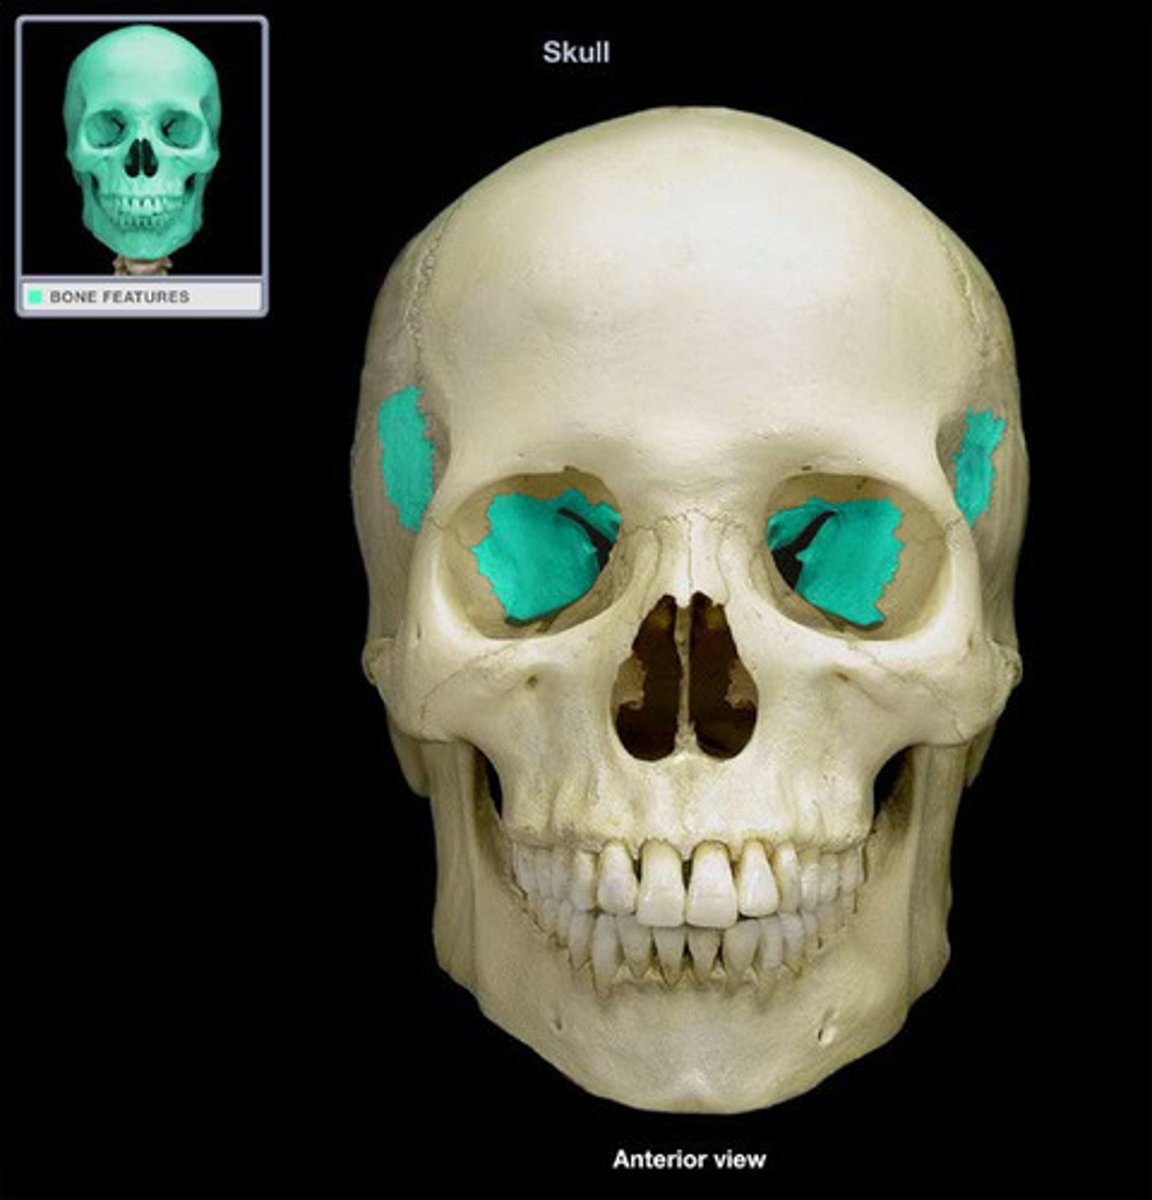

Ethmoid Bone

Ethmoid Bone

Lacrimal Bone